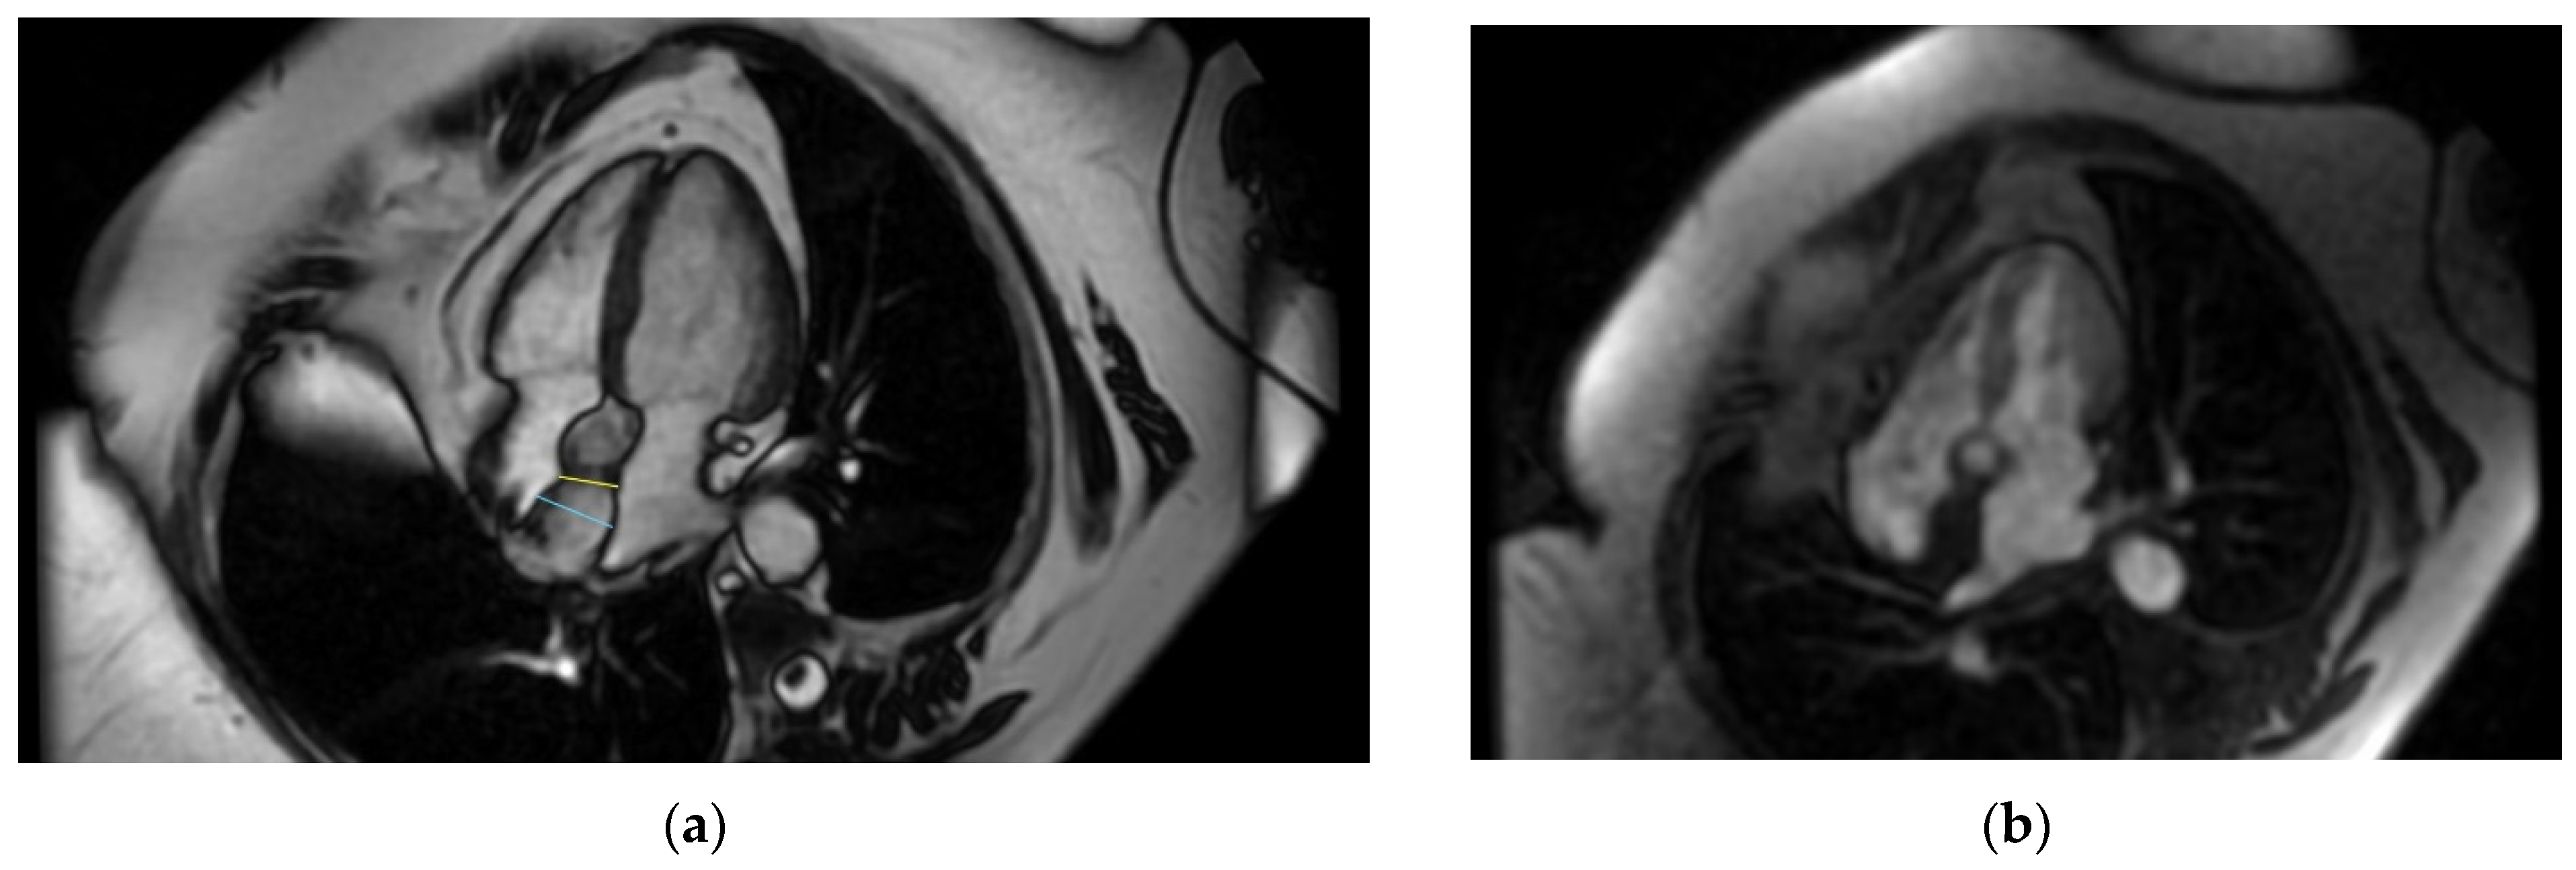

Even though the diagnosis was suspected, a cardiac magnetic resonance was performed in order to be accurate, given the implications a wrong diagnosis might have had. The “hourglass” aspect of the IAS with significant hypertrophy was confirmed in the cine-balanced steady-state-free precession (bSSFP) sequences. There was no contrast up-take at this level, suggesting a lack of vascularization, and the structure showed a high signal in T1 and a low/isointense signal in T2 with a very similar aspect to the very well-represented pericardial and mediastinal fat (Figure 4, Figure 5 and Figure 6). The diagnosis of lipomatous hypertrophy of the interatrial septum was established.

Figure 4.

Cardiac MRI. (a) Four-chamber-view, steady-state-free precession image revealing interatrial septal hypertrophy—25 mm with “chemical shift”; (b) perfusion image—no caption of contrast at first-pass contrast.

Figure 5.

Cardiac MRI. (a) Double-inversion-recovery T1 sequence (4 chambers) revealing a hyperintense interatrial septum suggestive of fat; (b) double-inversion T1 sequence with fat suppression revealing a hypointense interatrial septum.

Figure 6.

Cardiac MRI. (a) Triple-inversion-recovery T2 sequence of isointense interatrial septum; (b) late gadolinium enhancement (LGE)—enhancement in interatrial septum.